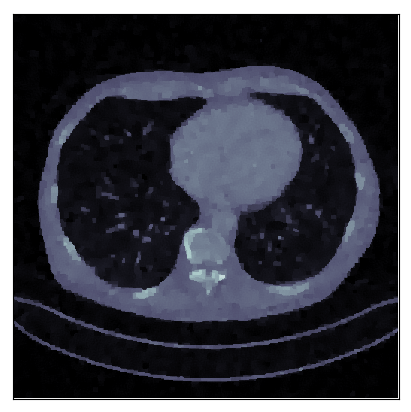

We consider the variational reconstruction framework for inverse problems and propose to learn a data-adaptive input-convex neural network (ICNN) as the regularization functional. The ICNN-based convex regularizer is trained adversarially to discern ground-truth images from unregularized reconstructions. Convexity of the regularizer is desirable since (i) one can establish analytical convergence guarantees for the corresponding variational reconstruction problem and (ii) devise efficient and provable algorithms for reconstruction. In particular, we show that the optimal solution to the variational problem converges to the ground-truth if the penalty parameter decays sub-linearly with respect to the norm of the noise. Further, we prove the existence of a sub-gradient-based algorithm that leads to a monotonically decreasing error in the parameter space with iterations. To demonstrate the performance of our approach for solving inverse problems, we consider the tasks of deblurring natural images and reconstructing images in computed tomography (CT), and show that the proposed convex regularizer is at least competitive with and sometimes superior to state-of-the-art data-driven techniques for inverse problems.